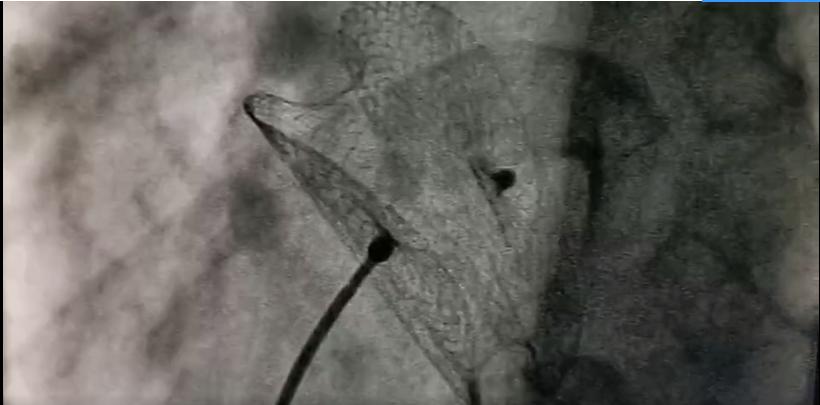

9月30日,在心外科苗齐主任的指导下,荆志成主任带领心内科先心病团队为王女士等3例患者进行了先天性心脏病介入封堵伞手术。介入封堵术的基本原理是用导管将收拢的伞片通过血管送达心脏缺损处,然后打开伞片,使伞片堵住两心房间的缺口,从而达到纠正血液流向、缓解右心及肺血管压力、减少患者心脏负荷的目的。

众所周知,手术必定有风险,尤其是在"刀尖上起舞"的心脏手术。介入封堵术需要术者与心内科超声心动图医生密切配合,共同完成。术者放置封堵伞时必须位置准确,分毫不差。同时,还要避免导丝及鞘管对心脏的刺激,否则会导致患者心律失常、甚至心脏骤停。手术对团队配合的要求也同样高。超声心动图医生是术者的眼睛,而术者是超声心动图医生的双手,两者齐心协力,手术才能成功。